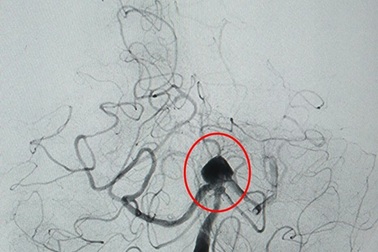

Đau đầu dữ dội vì túi phình khổng lồ ở động mạch nãoBệnh nhân Nguyễn Thị H. (52 tuổi, thôn 9, xã Hương Hòa, huyện Nam Đông, tỉnh Thừa Thiên Huế) nhập viện vì đau đầu dữ dội do túi phình động mạch não lớn.

Đau đầu đột ngột, biểu hiện của bệnh lý nguy hiểmNữ bệnh nhân nhập viện sau khi đột ngột đau đầu kèm theo nôn ói, chóng mặt. Qua thăm khám, chẩn đoán hình ảnh, bác sĩ phát hiện túi phình mạch máu khổng lồ ở não bị vỡ đe dọa tính mạng.

Phình mạch máu não: có thể chữa khỏi bằng can thiệp nội mạchNếu trước kia để điều trị phình mạch máu não, bệnh nhân phải trải qua cuộc phẫu thuật mở hộp sọ nặng nề, thì nay với phương pháp can thiệp nội mạch, bác sĩ có thể xử lý túi phình với một đường rạch nhỏ 1cm ở đùi.